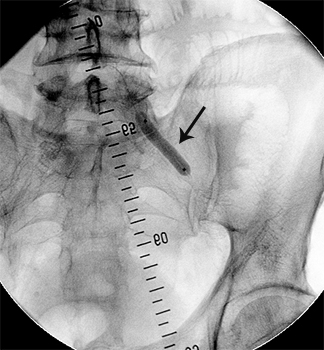

Ангіограми до та після стентування:

стеноз лівої ниркової артерії    балон, роздутий в зоні стенозу    відновлення отвору артерії

Субтотальний стеноз лівої

ниркової артерії

Балон-катетер зі стентом,

роздутий в зоні стенозу

Отвір артерії повністю відновлено